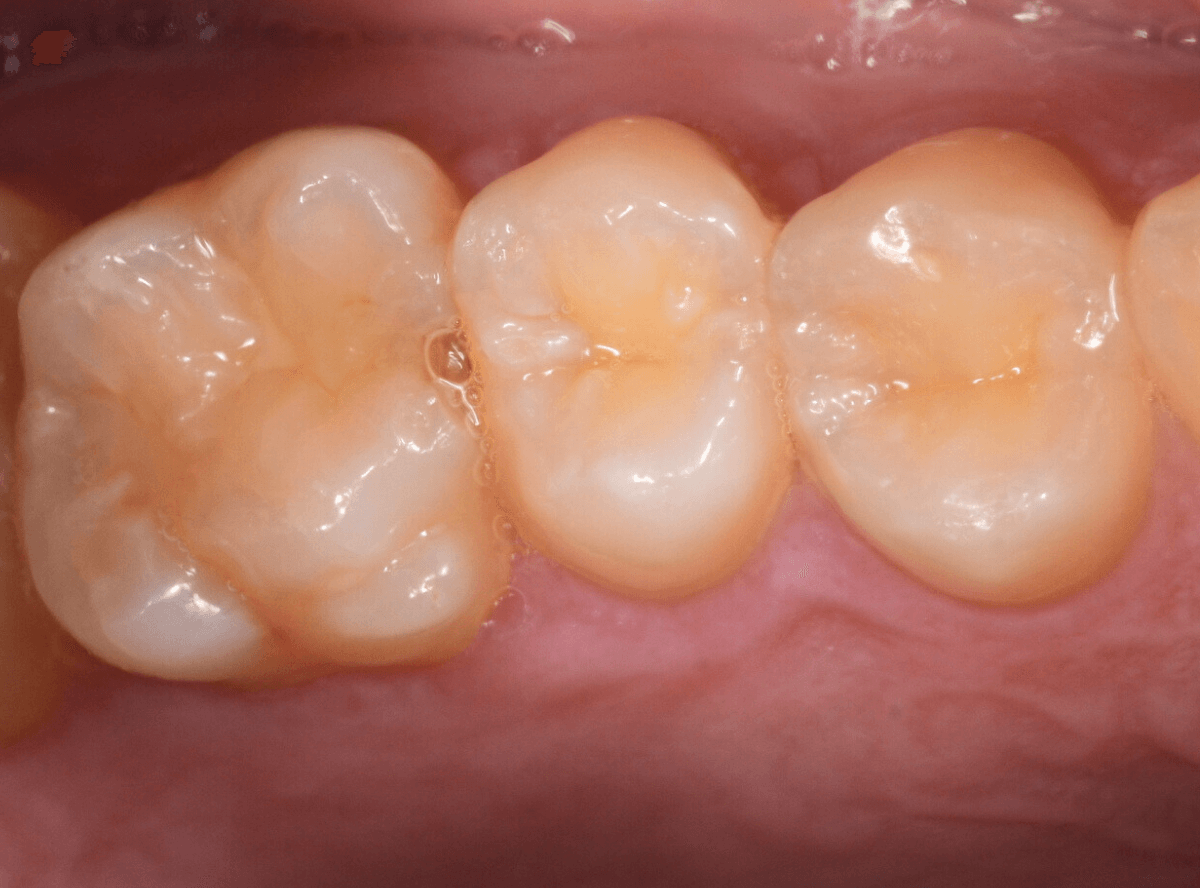

Case.1 奥歯のスキマが大きな虫歯!

他の歯の治療目的で来院された患者さんです。

全体検査の際、ちょっとこの歯、アヤシイなと思いましたが、確証はありませんでした。

(この写真で改めて見ると、かなりアヤシイと思いました)

レントゲン写真で確認すると、かなり大きな虫歯でした。

後日、改めて時間をお取りして、麻酔をかけて治療を開始です。

歯の表面を少し削ると、ボロッと虫歯が出てきました(>_<)

歯と歯の間の虫歯は、大抵は両方の歯に広がっている事がほとんどです。

今回のケースも、隣の歯まで、虫歯は広がっています。

最終的には、かなり神経に近いところまで虫歯が進んでいました。

もう少し遅かったら、危なかったと思います。

他の歯の治療で来院された事が、幸運でした。

しばらく経過観察した後、特に症状がありませんでしたので、隣の歯をレジンで治療後、ジルコニア・インレー(70,000円(税込み/2024年1月現在))で治療することにありました。

治療後の写真です。

特に症状もなく、審美性も高く治療することができました♪